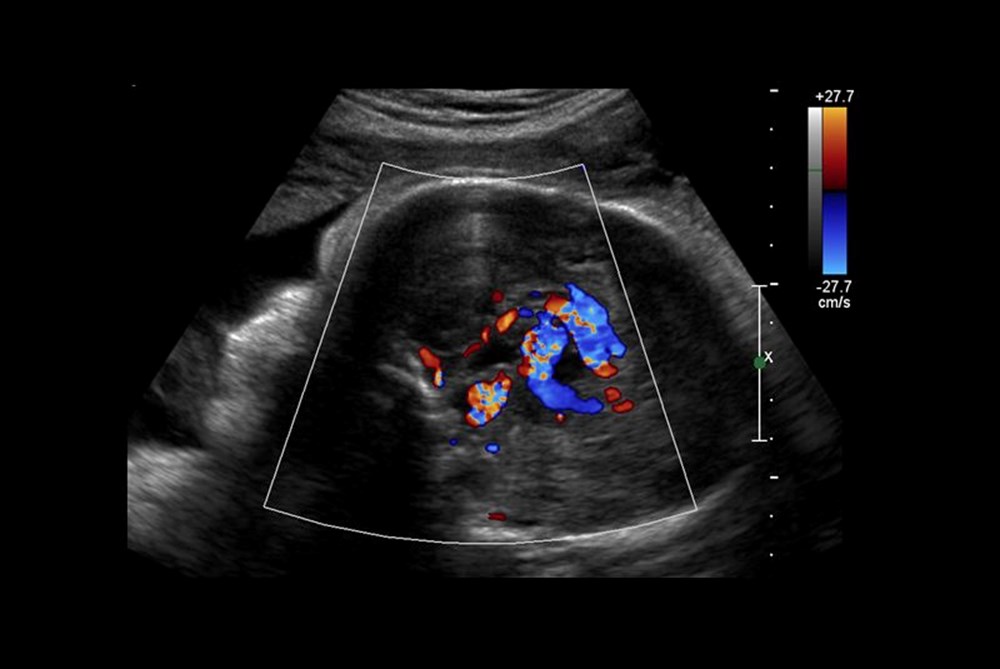

Diğer taraftan, operasyon kapsamında 10 sağlık görevlisinden oluşan bir ekip, annenin karnından uzun bir iğneyi bebeğin beyninin arterlerin etkilendiği kısmına yönlendirmek için ultrason kullandı. Doktorlar, daha sonra damarlara geri akışı engellemek için damar içine küçük bir madde enjekte etti.